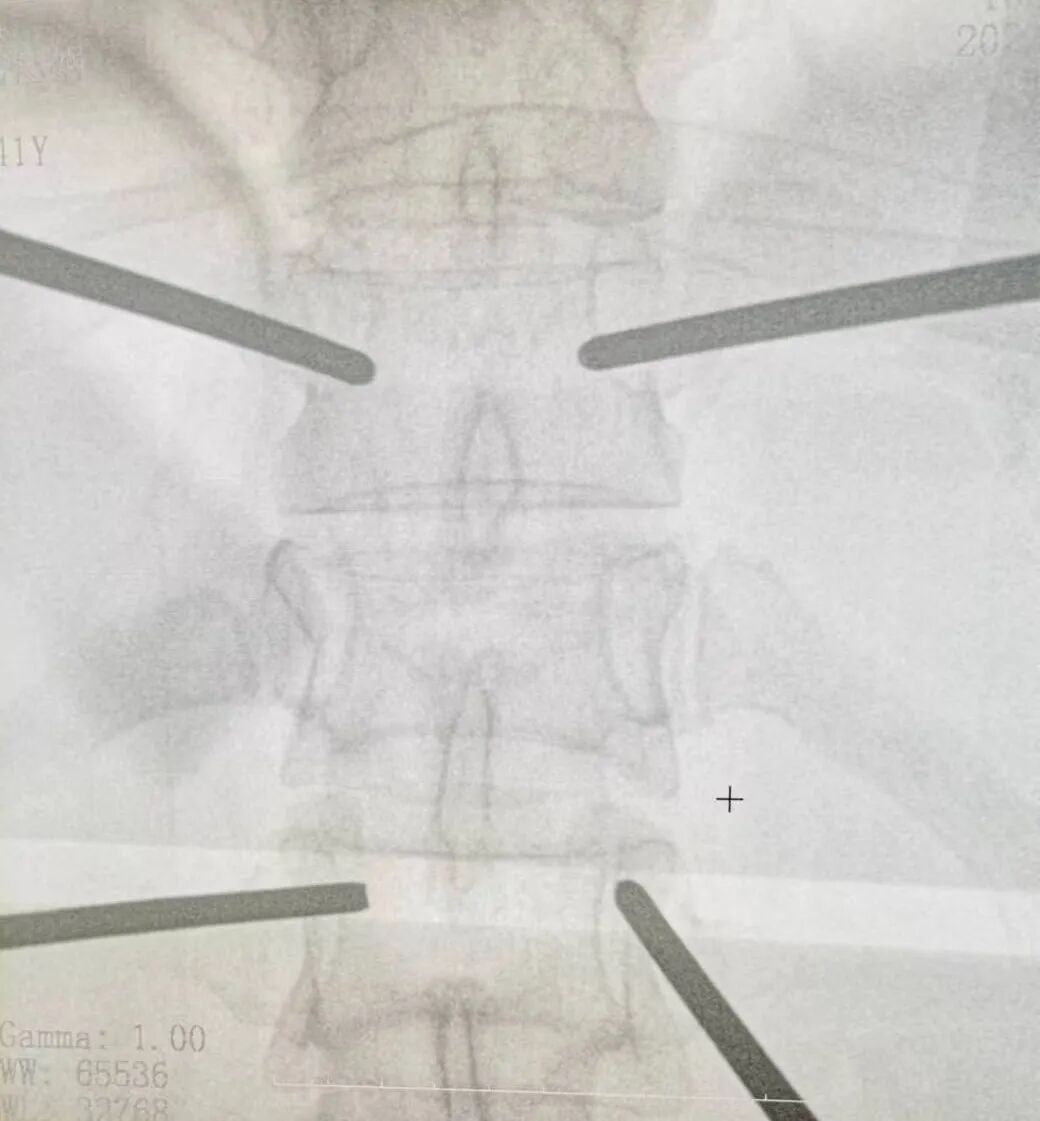

在麻醉科的通力协作下,由陈龙潭医生主刀,张林医生协助,为患者成功实施了微创经皮椎弓根螺钉内固定手术。术中,两位医生紧密配合,熟练运用C臂机透视定位,经皮肤打孔植入钉棒内固定系统,术后骨折复位满意,螺钉固定位置良好,椎体高度恢复满意。